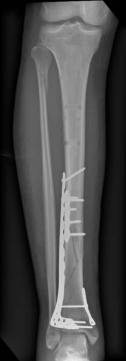

When a diaphyseal fracture propagates into the distal articular block, the injury transcends the typical treatment algorithms reserved for isolated tibial shaft fractures. Intramedullary nailing, the gold standard for diaphyseal fractures, becomes fraught with complications such as articular malreduction, propagation of intra-articular fracture lines, and inadequate distal fixation. Therefore, plate fixation—often utilizing minimally invasive percutaneous plate osteosynthesis (MIPPO) techniques—emerges as the primary definitive treatment modality. In the setting of an AO/OTA 43C3.3 fracture, where the articular surface is multifragmentary and completely dissociated from the diaphysis, the surgeon must meticulously reconstruct the joint surface before bridging the diaphyseal segment.

Digital templating is utilized to select the appropriate implant. For a fracture extending into the diaphysis, an extra-long anatomical distal tibia locking plate is required. The surgeon must determine whether an anterolateral or medial plate (or dual plating) will provide the optimal biomechanical construct based on the fracture morphology. The trajectory of the distal locking screws must be planned to provide a subchondral raft supporting the articular surface without penetrating the joint space. Furthermore, the availability of bone graft or orthobiologics must be confirmed, as elevating impacted articular segments will leave a metaphyseal void requiring structural support.

With the articular surface reconstituted, the surgeon's focus shifts to bridging the complex metaphyseal-diaphyseal dissociation. A pre-contoured anatomical locking plate is slid submuscularly or subcutaneously along the diaphysis using a MIPPO technique. The plate is positioned on the anterolateral or medial surface, depending on the preoperative plan and soft tissue constraints.

Image

The distal portion of the plate is secured to the reconstructed articular block. It is imperative that the distal locking screws are placed parallel to the joint space, forming a rigid subchondral raft that supports the articular cartilage. Fluoroscopy is utilized extensively to ensure no screws have penetrated the joint. Once the distal block is secured to the plate, the diaphyseal segment is aligned. Length, alignment, and rotation are restored using manual traction or the femoral distractor. The proximal portion of the plate is then secured to the diaphysis using a combination of non-locking screws (to pull the bone to the plate) and locking screws (to create a fixed-angle construct). The working length of the plate is maximized by leaving several screw holes empty over the zone of comminution, promoting secondary bone healing.